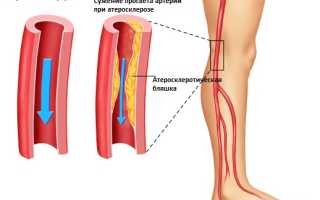

К врожденным причинам относится недоразвитие аорты и формирование фиброзно-мышечной дисплазии в период внутриутробного развития. Приобретенные состояния, возникающие с возрастом, включают атеросклероз артерий, постэмболитический тромбоз и аортоартериит. Наиболее распространенной причиной окклюзии является атеросклероз.

Развитие заболевания зависит от степени поражения аорты и ее подвздошных ветвей. Со временем нижние конечности и внутренние органы, находящиеся в области таза, начинают получать все меньше крови, кислорода и питательных веществ. Участки выше сужения перегружаются, а в нижних конечностях постепенно развивается кислородное голодание, известное как ишемия.

Атеросклеротическая бляшка.

Наиболее заметные изменения, связанные с атеросклерозом, проявляются в области деления аорты и в местах ответвления подвздошной артерии.

- На внутренних стенках сосудов образуются отложения кальция (кальциноз). Кальцинаты состоят из мертвых тканей, погибших в результате инфекции или травмы. Кальциноз приводит к хрупкости сосудов, что увеличивает риск их разрыва при повышении давления и напряжении. Удалить кальцинаты из организма невозможно.

- Еще одно явление, связанное с атеросклерозом, — это пристеночный тромбоз. При наличии неспецифического аортоартериита больше всего страдает аорта. Ее стенки подвергаются кальцинозу, а участки воспаления утолщаются.